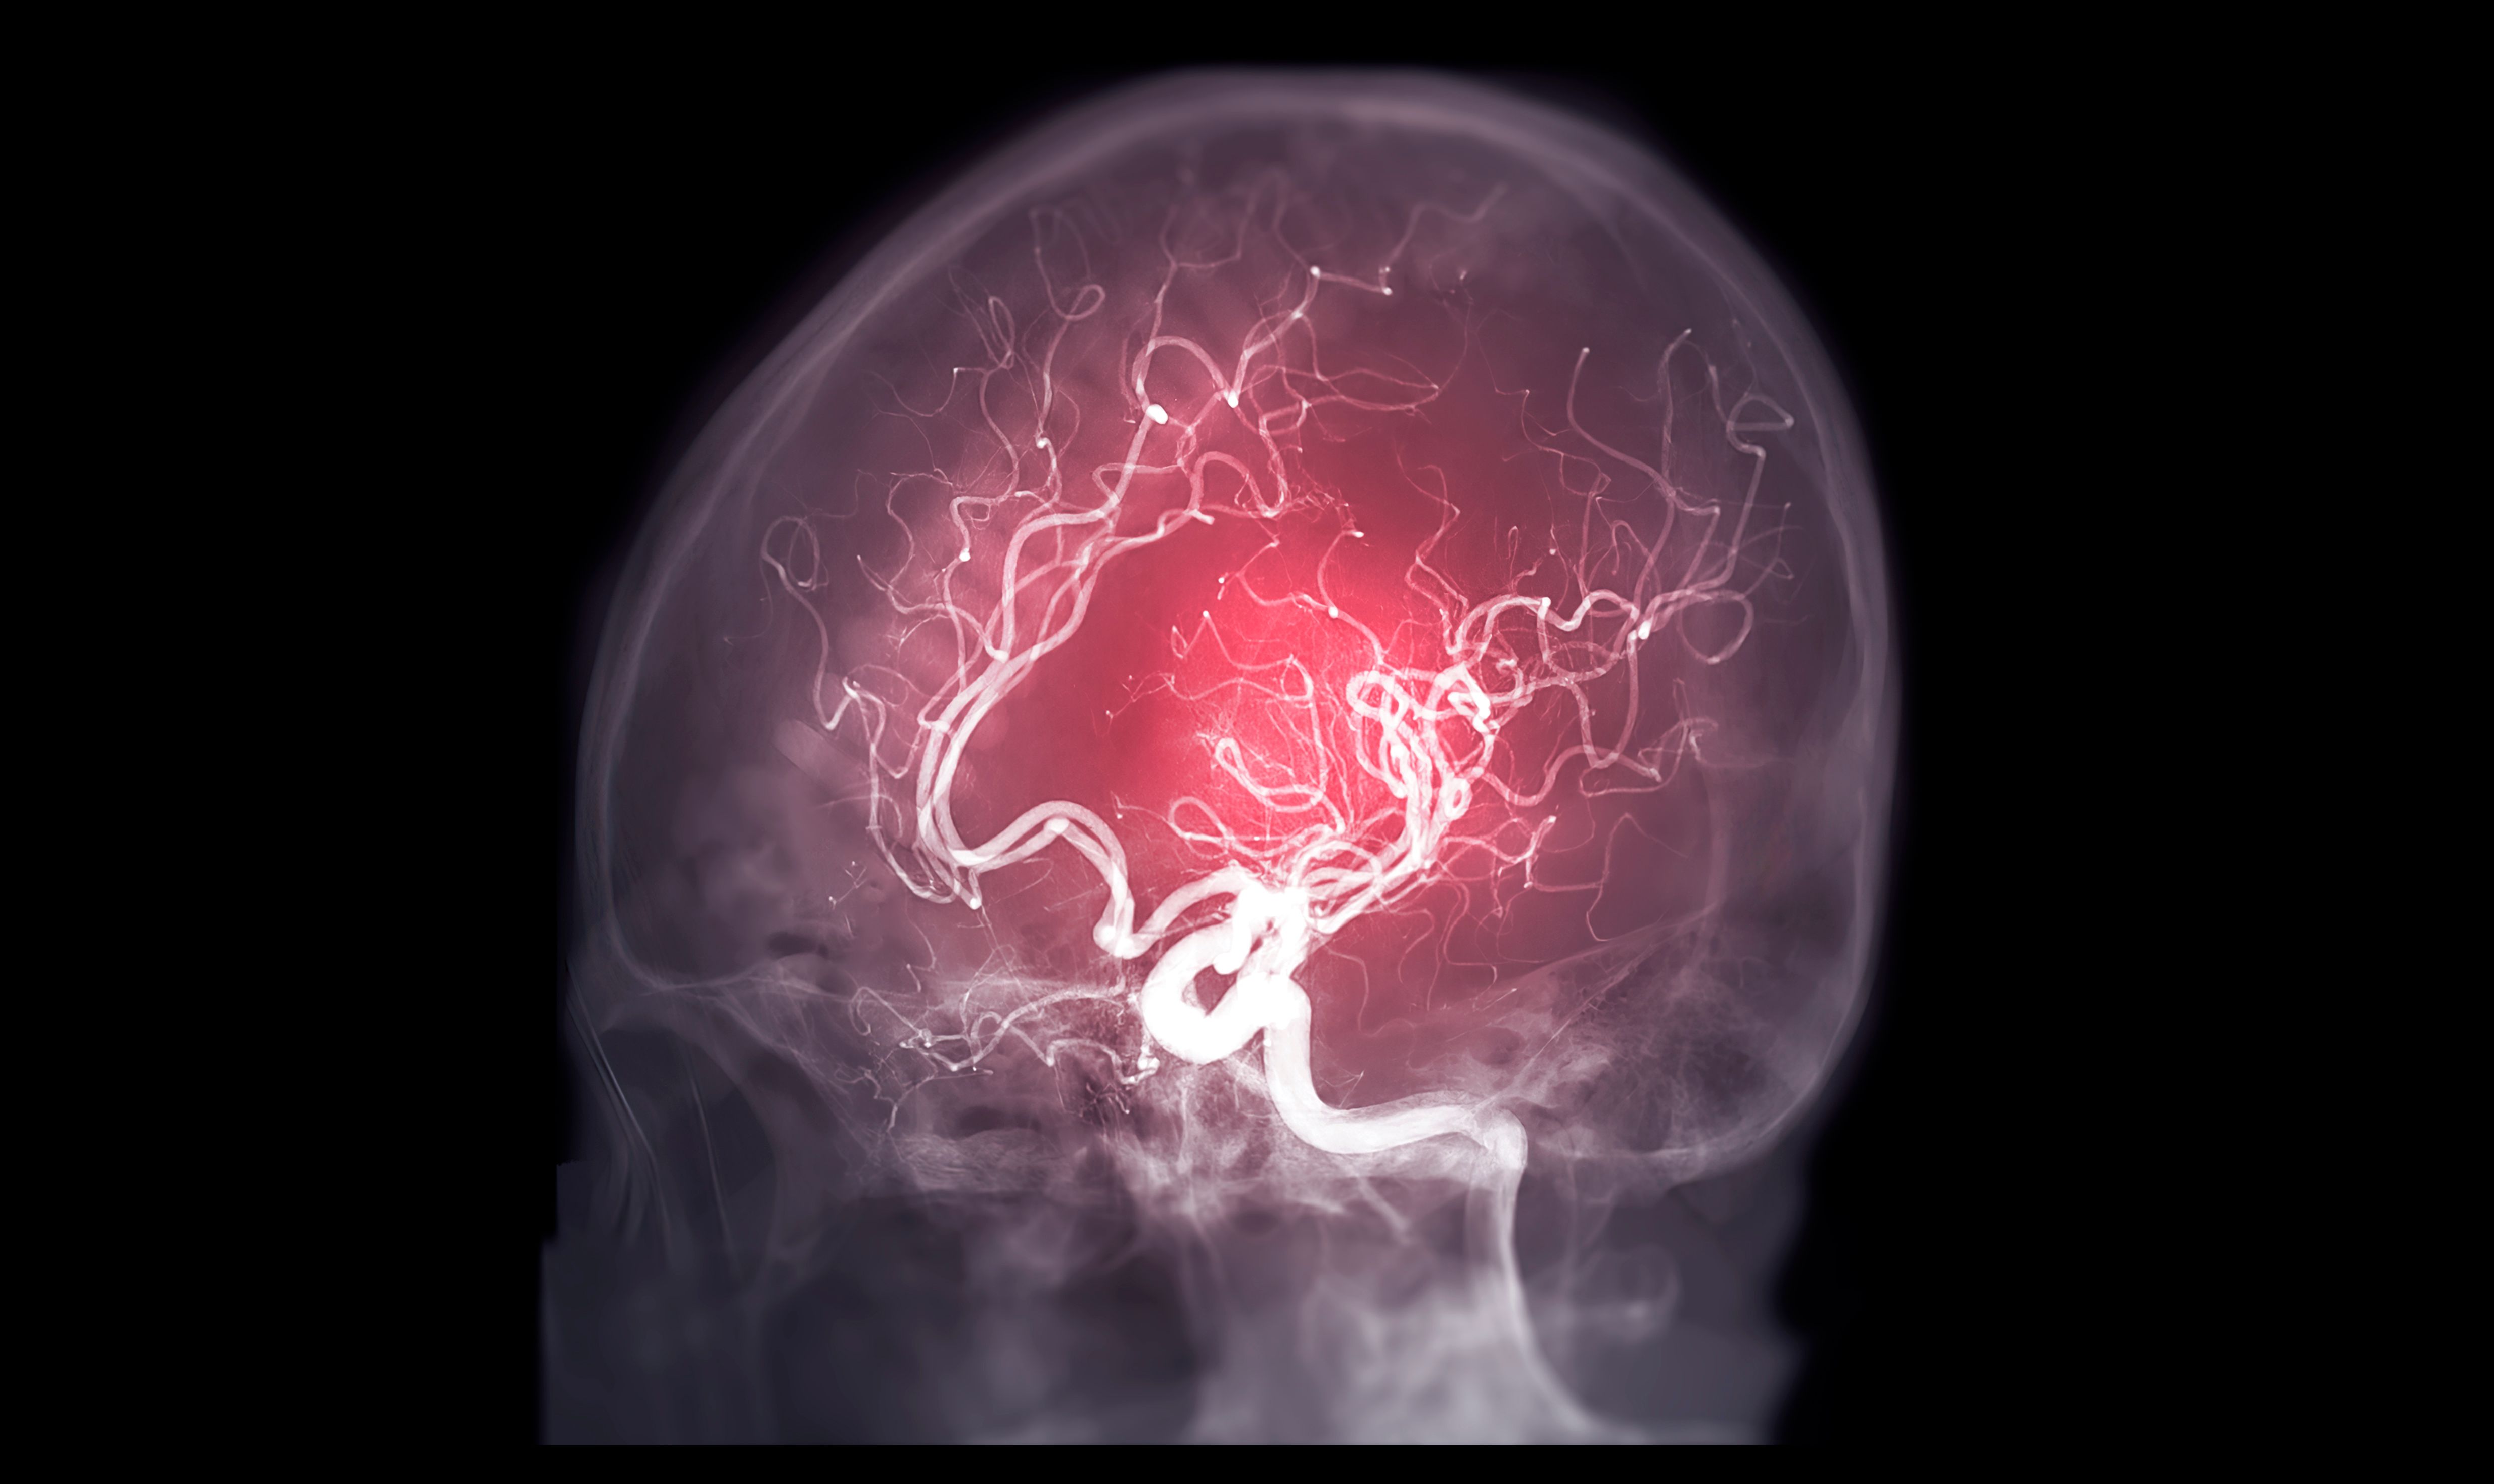

- Interventionelle Radiologie: Minimal-invasive Verfahren zur Behandlung verschiedener medizinischer Zustände.